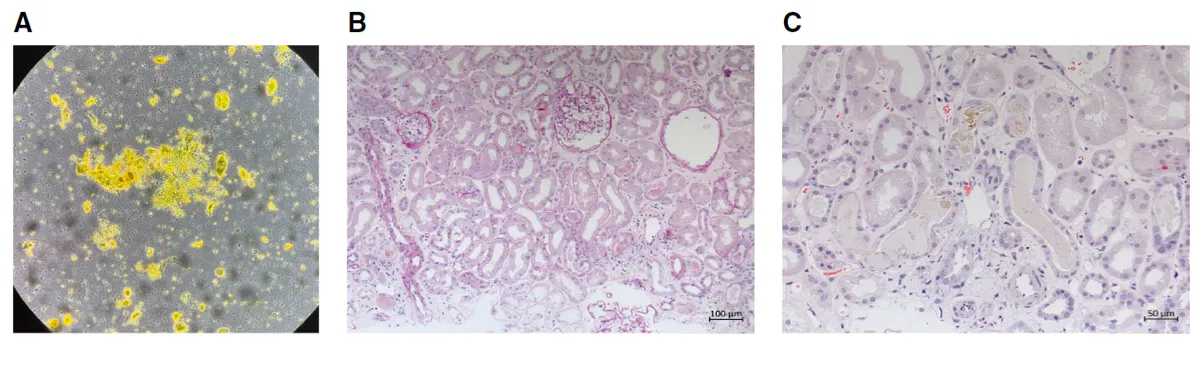

**Figura 1.** Achados urinários e histológicos da biópsia renal. (A) O sedimento urinário mostra células epiteliais tubulares, cilindros granulares corados por bile e cristais de leucina. (B) Os túbulos renais apresentam células epiteliais achatadas e perda da borda em escova (NTA). (C) Os túbulos exibem cilindros amarelo-esverdeados corados por bile (H&E).

Foi realizado biópsia confirmando existência de necrose tubular aguda com cilindros biliares, compatível com Nefropatia Colêmica.

O sedimento urinário revelou cilindro biliares, cristais de leucina e células tubulares — achados que direcionam o raciocínio para lesão tubular por pigmentos.

A biópsia mostrou:

• necrose tubular aguda difusa,

• cilindros biliares verde-amarelados ocupando túbulos,

…selando o diagnóstico de Nefropatia Colêmica.